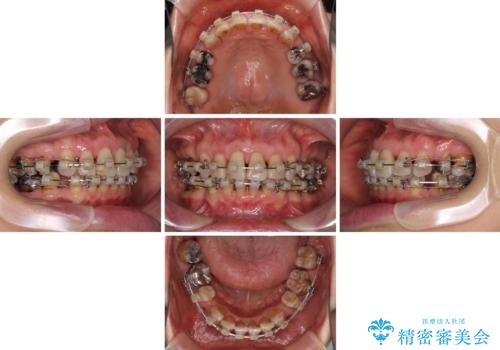

- 矯正装置

- クリアブラケット

- 2年7ヶ月

- 突出した口元を引っ込めることを希望して来院された患者様です。

上下左右第一小臼歯4本を抜歯して、口元を改善するワイヤー矯正を行うこととしました。